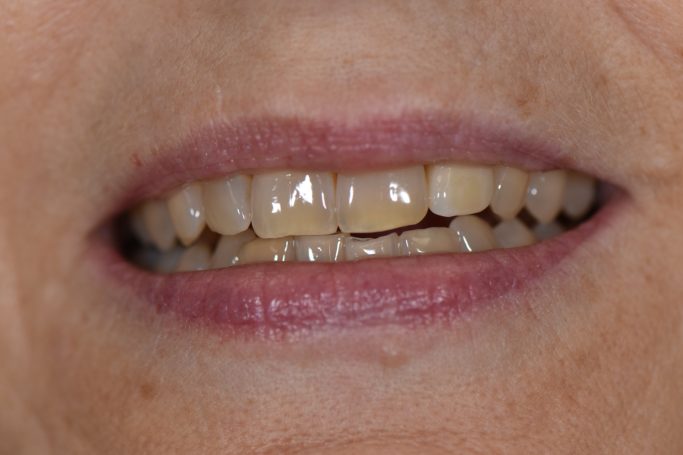

Teleskopierende Oberkieferbrücke mit Vorher- und Nachher-Situation des Patienten.

Teleskopierende Oberkieferbrücke. Wie die eigenen Zähne, aber einfach zu reinigen.